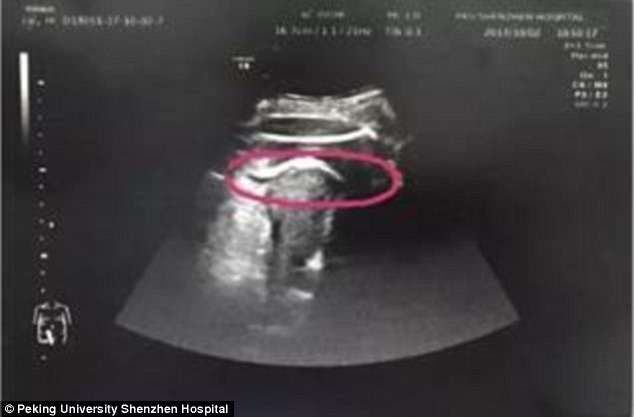

Người phụ nữ mang thai 8 tháng phải nhập viện cấp cứu trong tình trạng nguy kịch. Sau khi thai phụ được các bác sĩ tiến hành siêu âm. Hình ảnh siêu âm cho thấy tử cung của sản phụ bị thai nhi đạp rách.

Sáng 2/10/2017, Zhang, đang mang thai tuần thứ 35 thấy đau bụng dữ dội. 5 tiếng sau đó, cô được đưa vào bệnh viện tỉnh Thâm Quyến. Zhang nói trước đây mình từng phẫu thuật u xơ nên các bác sỹ ngay lập tức đưa cô đi siêu âm vì nghi tử cung của sản phụ bị vỡ.

Kết quả siêu âm cho thấy, tử cung bị rách như các bác sỹ phỏng đoán và nguyên nhân do thai nhi 35 tuần tuổi đạp vỡ. Đứa trẻ thậm chí còn thò chân sang khoang bụng khiến đùi bị mắc kẹt ở thành tử cung.